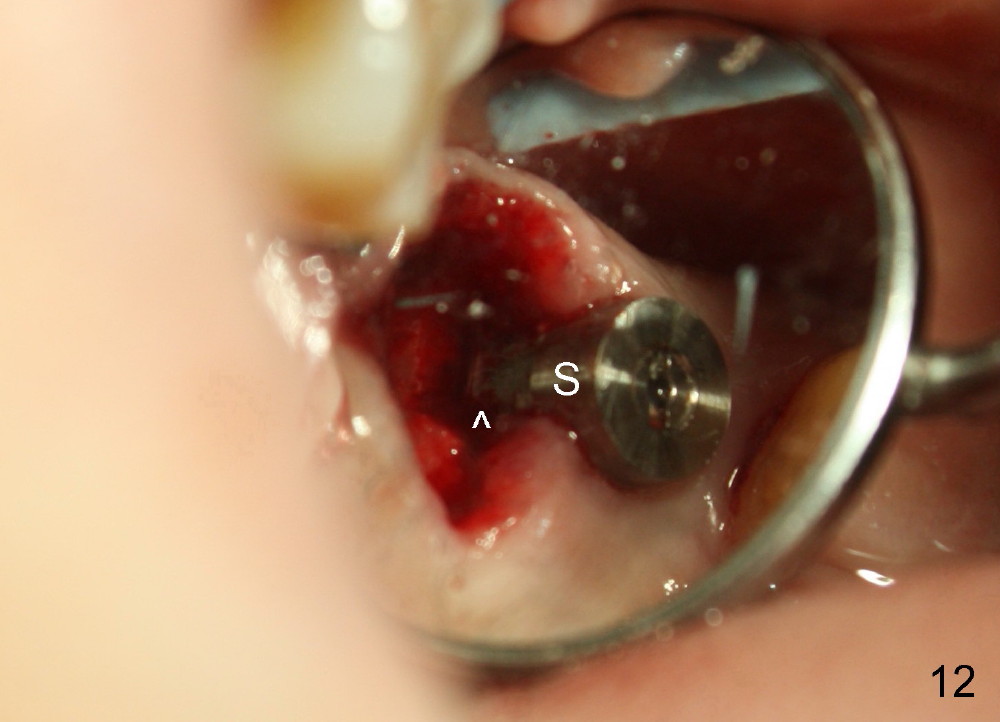

Postop, the patient has a car accident. She does not return for followup until 11 months later. The implant is stable. The neighboring third molar has caries (Fig.11 *). When it is extracted, the distal threads of the implant are found to be exposed (apical to ^ in Fig.12). A synthetic bone graft is placed to cover the exposed threads, followed by insertion of a collagen plug (Fig.13).